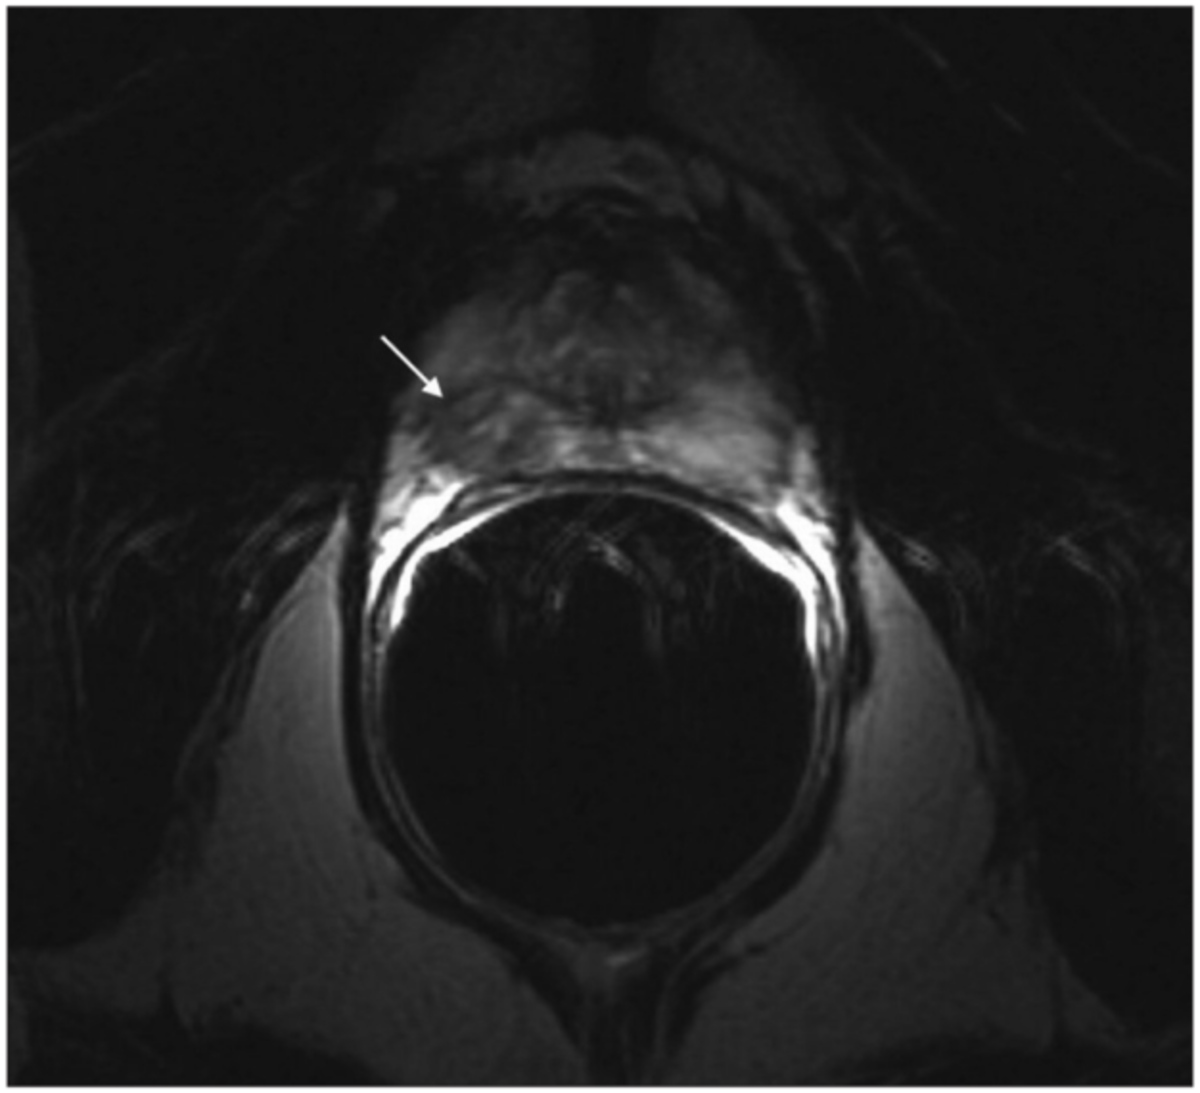

Most clinically important prostate tumours are adenocarcinomas. On MRI, they tend to be dark on T2, show restricted diffusion (low ADC), and often enhance early with contrast, but appearances vary by zone, grade, and size26.

Most prostate cancers are acinar adenocarcinomas arising in the peripheral zone; on mpMRI, these usually appear as focal, round or oval low-signal areas on T2-weighted images, with marked diffusion restriction and corresponding low ADC values27.

Clinically significant cancers (higher grade, larger volume) tend to show more pronounced diffusion restriction, with very low ADC and very bright high-b-value DWI signal, and more conspicuous, early contrast uptake on dynamic imaging30. These lesions are more likely to be scored PI-RADS 4-5 and correlate with higher Gleason/ISUP grades on biopsy.